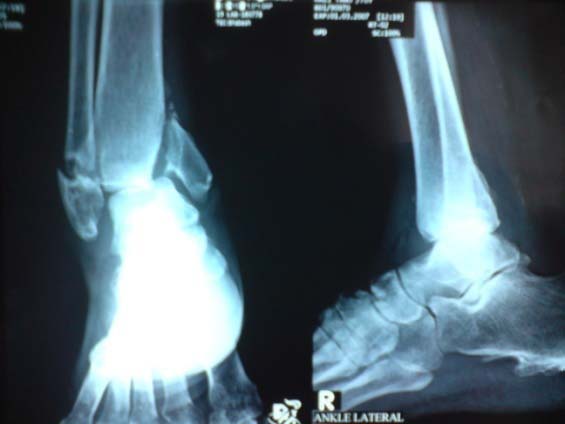

A 80-year-old man with type 2 diabetes of 15 years duration was reffered to BIRDEM hospital OPD with a 7 days history of dull pain and swelling in his right ankle and foot following a minor trauma. He was unable to walk and his ankle was grossly deformed and unstable. There were no signs of inflammation, and sensation in the foot including pain and touch was reduced. He was known to have neuropathy and peripheral vascular disease with poor control of blood sugar. Intermittent pain and swelling in the foot had started six months previously. He was treated by doctors with diagnosis of ankle arthritis and osteomyelitis on different ocassions. Several courses of antibiotics and analgesics were prescribed. Two separate ankle and foot X-rays were done in BIRDEM, which revealed gross osteopenia, soft tissue swelling and fracture-dislocation of the right ankle with bony fragmentation of the mid foot (Fig.1). His inflammatory markers of the blood were unremarkable.

Fig. 1. Pre-operative X-ray:Fracture and dislocation in a right ankle Charcot joint